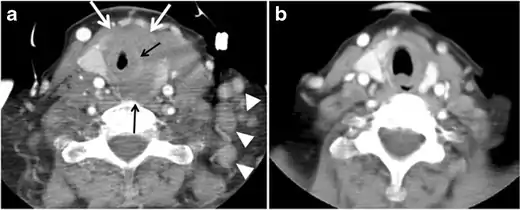

Surgery is the primary mode of treatment for DTCs. Post total thyroidectomy radioactive iodine (RAI) ablation is an option, especially in patients with distant metastasis, tumours larger than 4 cm, or extra-thyroidal disease extension. Ultrasound examination is usually adequate in evaluating primary tumours and cervical lymph nodes. Preoperative cross-sectional imaging with CT or MRI is indicated if there is a concern for local invasion that may alter the patient's staging as well as surgical approach (Figs. 4, 55 and 6)6) . Some thyroid primaries may be small, diffuse, or multifocal and therefore may be occult on imaging (Fig. 4) .[1]

The radiologist must evaluate the central structures draping the thyroid gland including the trachea, oesophagus, larynx, and pharynx, as well as the recurrent laryngeal nerve. Invasion is suspected if the thyroid mass abuts the airway or oesophagus for more than 180 degrees. Luminal deformity, mucosal thickening and mucosal focal irregularity are more specific indicators of invasion. Obliteration of the fat planes of the tracheoesophageal groove in three axial images and signs of vocal cord paralysis are indicative of recurrent laryngeal nerve invasion. Invasion of these central structures meets the criteria for T4a disease (Figs. 5 and and6)6).[1]

Arterial invasion constitutes T4b disease, which may preclude curative surgery. More than 180 degrees of arterial encasement is suggestive of invasion, however, arterial deformity or narrowing is much more suspicious for invasion. The carotid artery is the most commonly involved artery; however, the mediastinal vessels should also be examined. Encasement of the carotid artery or mediastinal vessels for more than 270 degrees is unlikely to be resectable. On the other hand, occlusion or effacement of the internal jugular vein can occur without invasion and does not influence surgical resectability or staging. Asymmetry of the strap muscle and the tumour abutting its external surface are signs of an invasion. However, invasion of the pre-vertebral musculature is more challenging, as a large lesion can compress the muscle without invasion (Figs. 5 and and6)6).[1]

Finally, the possibility of metastatic disease should be excluded. PTCs and medullary thyroid carcinomas tend to metastasize to regional lymph nodes. According to the AJCC/UICC TNM staging system, the nodal stage is classified by site: N1a indicates level VI nodal involvement, including paratracheal nodes; N1b indicates unilateral or bilateral lateral cervical nodal disease or superior mediastinal nodal disease (Figs. 4, 55 and and6)6).[1]